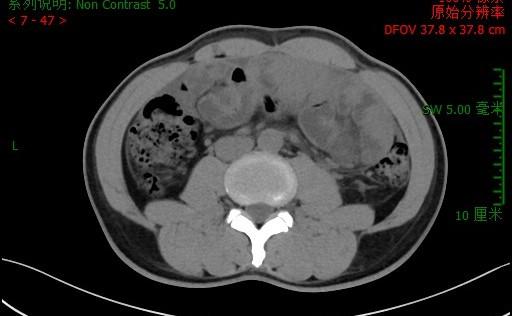

李先生入院腹部CT

南院区普外科检查及会诊后发现,患者左下腹有一个25*20cm的硬质包块活动度差,有局限性压痛、反跳痛;CT检查显示小肠系膜纠集,周围线状包裹,提示“腹茧症可能,伴小肠不全梗阻”;患者肿瘤标志物、结核指标、自身免疫指标、胃肠镜等检验检查均为阴性。经讨论后,大家一致认为,造成李先生呕吐、腹痛、停止排便的“元凶”是腹茧症,患者小肠被纤维包膜层层包裹,失去蠕动的功能,因此演化为不完全性粘连性肠梗阻。手术剥离肠管外周增厚的纤维膜是解除梗阻、恢复正常进食的唯一途径。